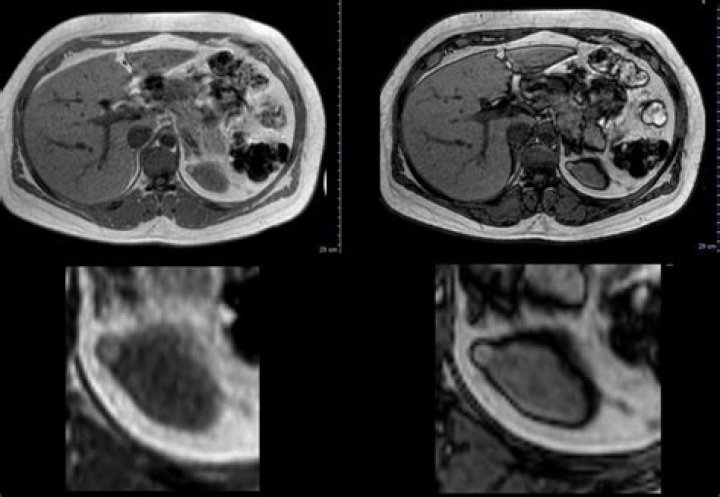

The sonographic appearance in such cases can mimic a solid ovarian neoplasm. Follow-up sonography will show dramatic changes within the hemorrhagic cyst usually in 4 to 6 weeks. Besides color flow imaging will show lack of flow within the hemorrhagic cyst.